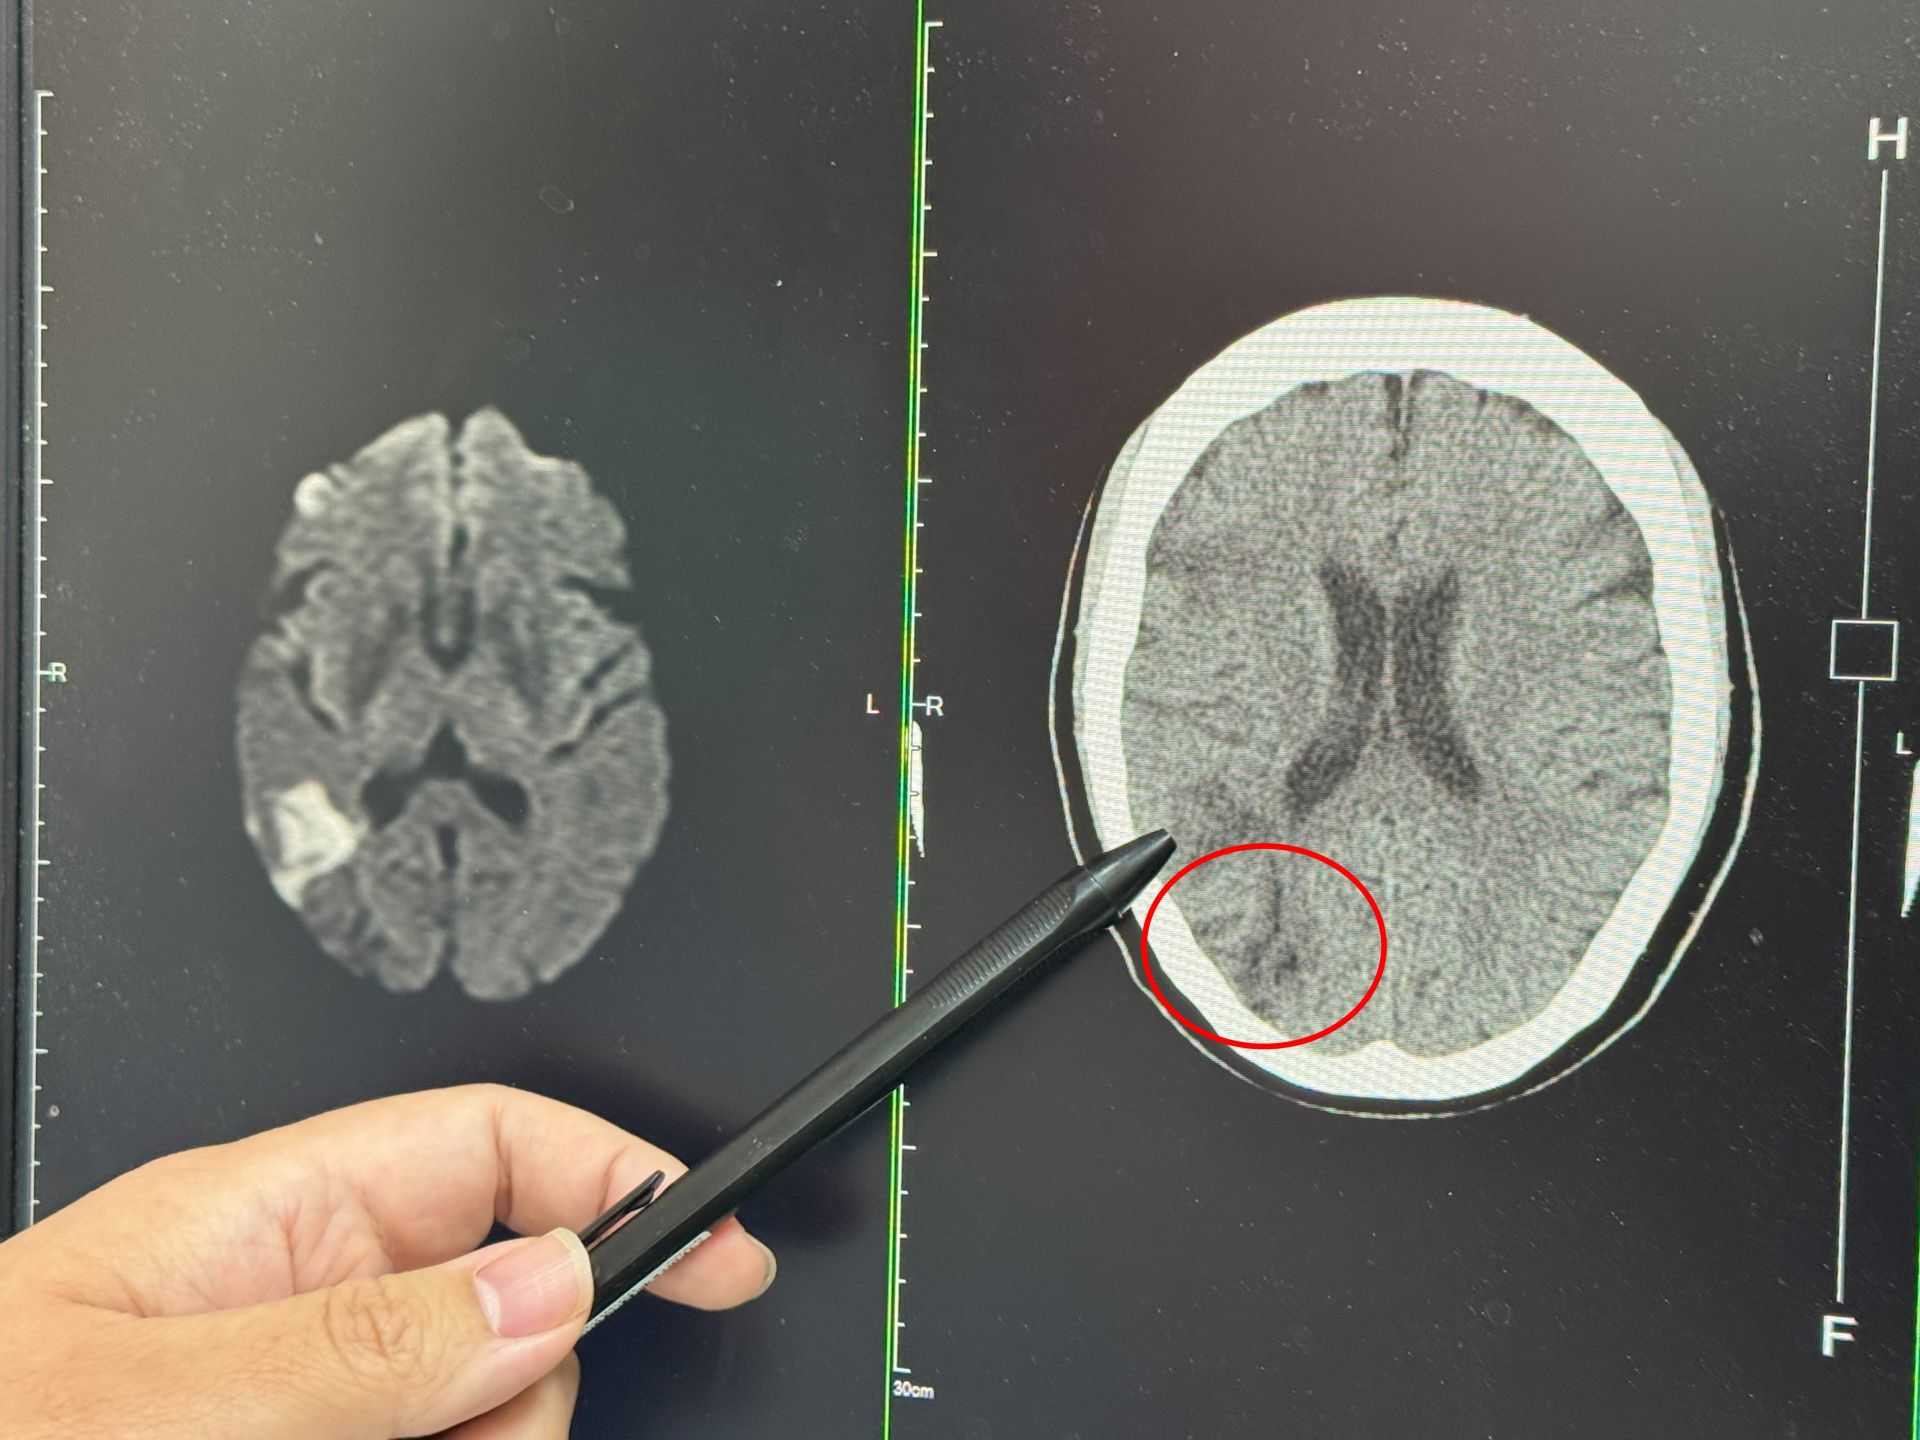

一名婦人右側中大腦動脈阻塞而影響到視野。大甲李綜合提供

張峻誠說,聽完患者的描述,研判此症狀即是中風,先安排電腦斷層檢查,果然看到右邊中大腦動脈阻塞,為了確認阻塞範圍,進一步做核磁共振,詳細判讀後發現,婦人當時眼睛出現模糊時已經初次中風,只是比較幸運範圍較小,沒有出現手腳無力、無法行走的情形。